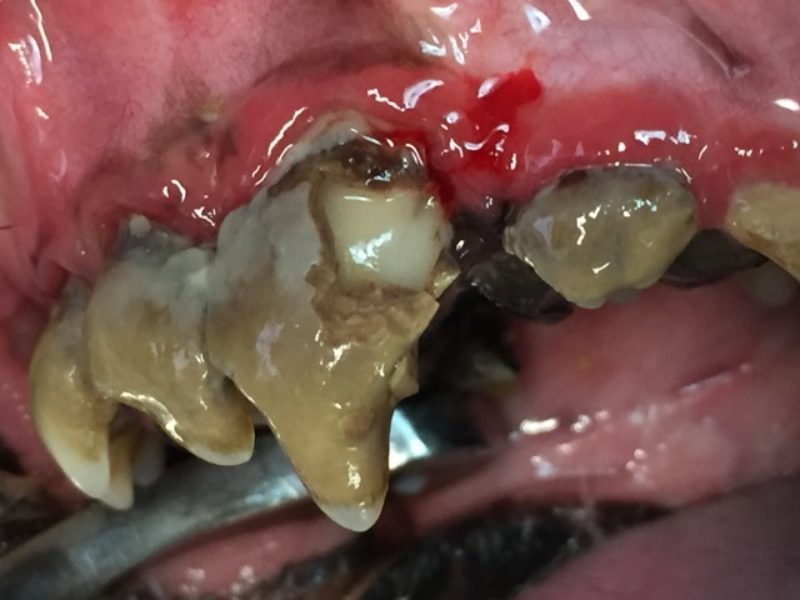

Durch den Zahnstein kommt es schließlich zu Entzündungen des angrenzenden Zahnhalteapparates. Zahnfleisch- und Knochenschwund erleichtern dem Zahnstein, sich noch weiter auszubreiten. Die zum Teil frei liegenden Zahnurzeln werden nun ebenfalls befallen. Dort wird der Belag allerdings als Konkrement bezeichnet und führt dazu, dass der Zahn keinen Halt mehr hat.